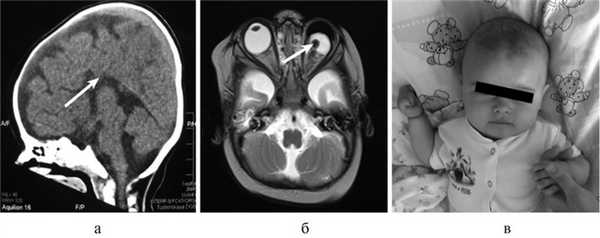

Рис. 1. КТ и МРТ головного мозга (сагиттальная, фронтальная проекции) и внешний вид больной Т., 8 мес. а — КТ: АМТ (стрелка); б — микрофтальм слева на МРТ (стрелка); в — внешний вид пациентки с множественными стигмами дизэмбриогенеза.